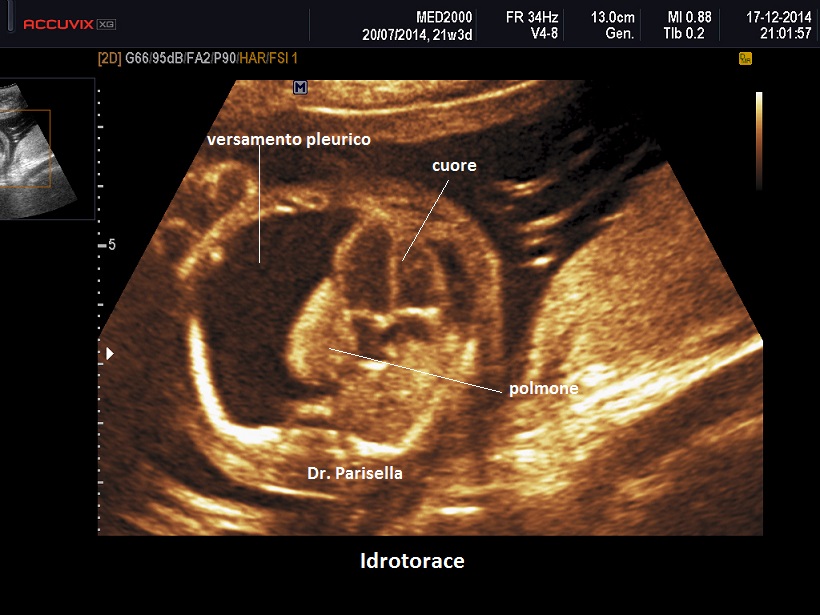

• effusione pleurica

Un primo orientamento sulle cause di idrope può essere fatto attraverso la localizzazione dell'accumulo di liquido: un accumulo generalizzato sin dal principio orienta verso una causa sistemica come l'anemia, mentre un accumulo inizialmente localizzato porta ad orientarsi verso una patologia locale ( es.: versamento pleurico >>>> Malformazione Adenomatoide Cistica Congenita del polmone).